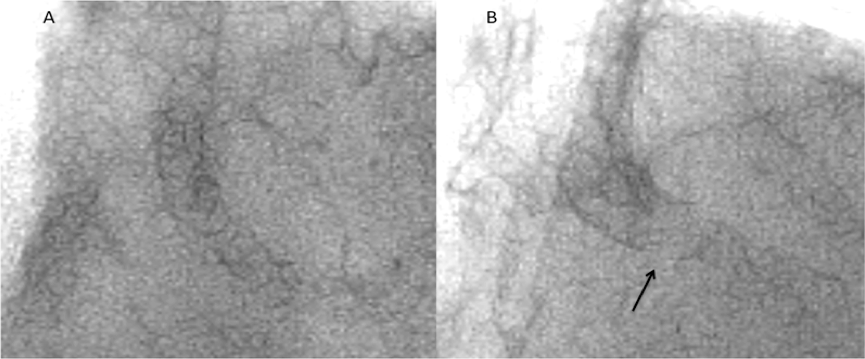

Figure 7. Comparison of plain fluoroscopic images (A) immediately after Nobori stent deployment and (B) at the 9-month follow-up exam, showing a gap in the stent strut (arrowhead) (click thumbnail to view larger image).

Nine months after the Nobori stent implantation, the patient was admitted for chest pain on effort. Right coronary angiography revealed a focal significant ISR of the Nobori stent (Figure 6A), and plain fluoroscopic images showed a gap in the strut in the middle of the Nobori stent, suggesting SF (Figure 7B). The fractured segment was treated with a 3.0 × 12 mm PROMUS Element stent (Boston Scientific). No further imaging was possible because of severe calcification and tortuosity. Post-stenting angiography revealed an excellent result (Figure 6B).